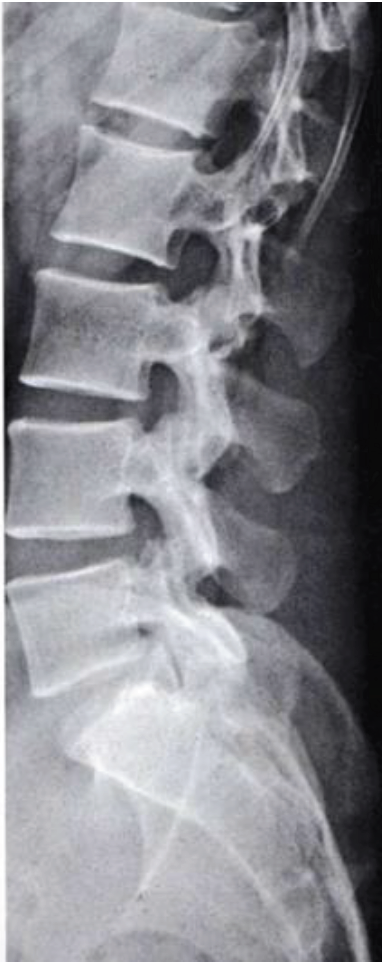

What is this view in the lumbars? Whart views are missing?

Lateral

MISSING

AP (tilt 15 degree SIJ)

Lateral on other side

Oblique R & L

L5/S1 spot (AP and Lat)